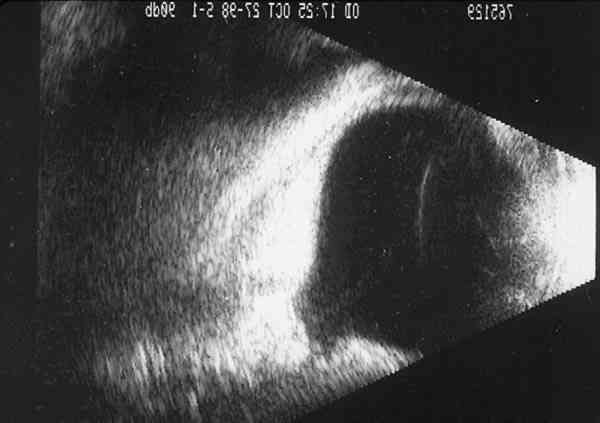

Figura 7

DETALLE ECOGRÁFICO DE LA EMERGENCIA DE LA ARTERIA HIALOIDEA PERSISTENTE DESDE LA PAPILA EXCAVADA.